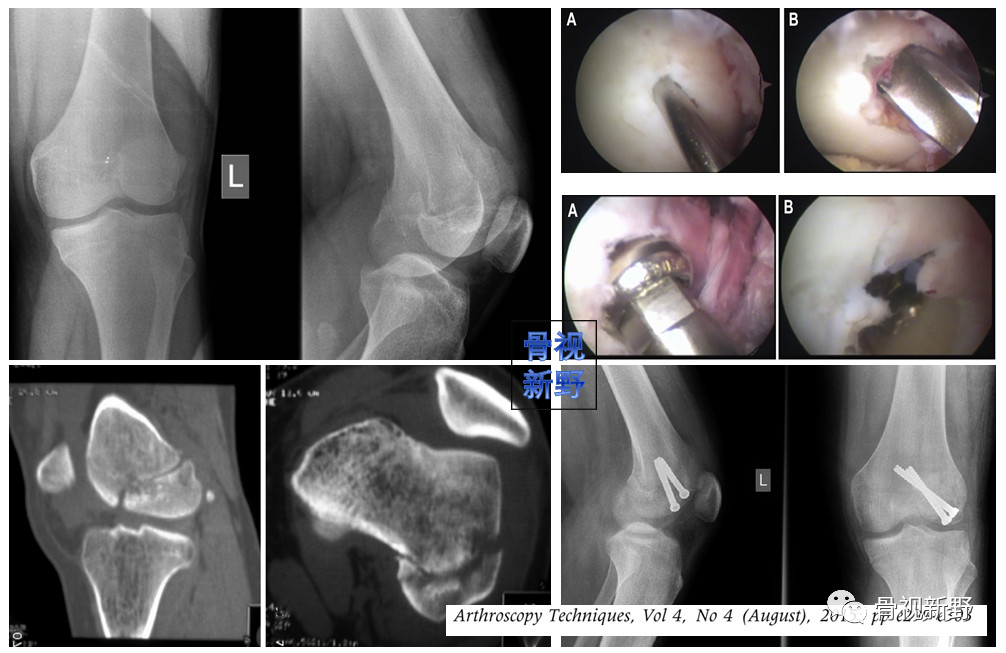

影像诊断:部分Hoffa骨折X线片不能提供明确的诊断,漏诊率较高。需要CT或MRI检查,并根据患者的病史、查体及影像学检查予以确诊。

部分Hoffa骨折普通X光片易漏诊

CT扫描在矢状位、轴位容易发现骨折及骨折线的走形方向

关节镜微创入路

关节镜微创手术可减少软组织剥离和出血量,术后关节功能及软组织恢复较好。但目前仅有少数个案报道,尚并无充分证据支持关节镜辅助Hoffa骨折。